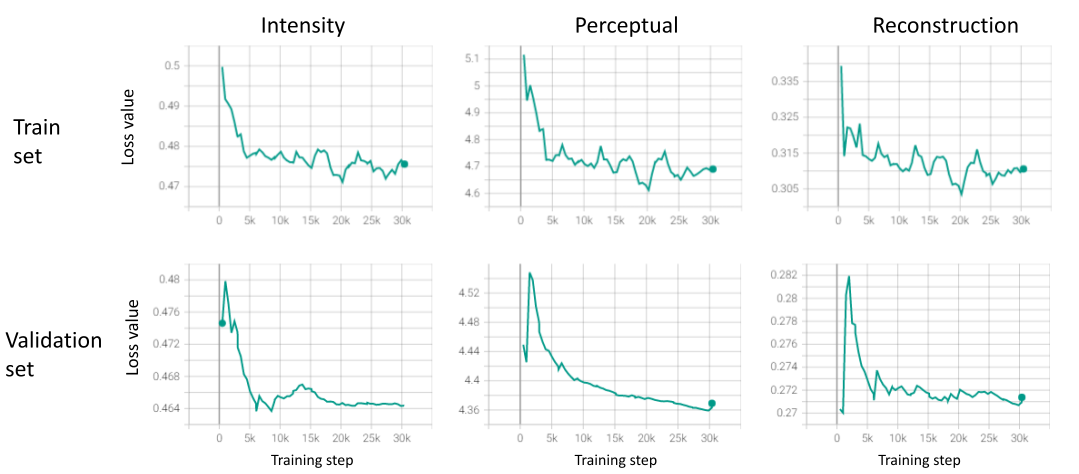

blackFig.6 presents the loss values during the pre-training phase. As can be seen, the performance on the validation and training sets is highly correlated, the values of all three losses are mostly decreasing monotonically, and their values are within one order of magnitude from each other.